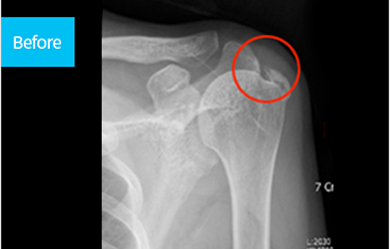

석회제거술이란?

퇴행성 변화로 인해 어깨 힘줄 세포가 괴사하면서 그 조직에 석회질이 침착하게 됩니다.

이로 인해 발생하는 질환인 석회성 건염의 치료 방법 중 하나가

석회성 물질을 제거하고 염증 부위를 절제하는 ‘석회제거술’입니다.

석회화건염

어깨의 회전근개(힘줄) 주변에 석회 물질이 생성되어 극심한 통증을 유발하는 질환을 말합니다.

주로 40~50대 이후 여성에게서 발생하며, 이는 어깨 힘줄의 퇴행성 변화와 관련이 있습니다.

침착된 석회가 치료 후 없어진 모습

before img after img